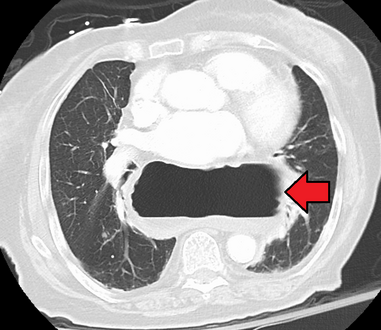

يتم تشخيص الفتق الحجابي هذا بشكل أساسي من خلال مستوى الهواء والسائل (الموضح بواسطة الأسهم).

فتق حجابي كبير كما يظهر بالتصوير المقطعي المحوسب.

-